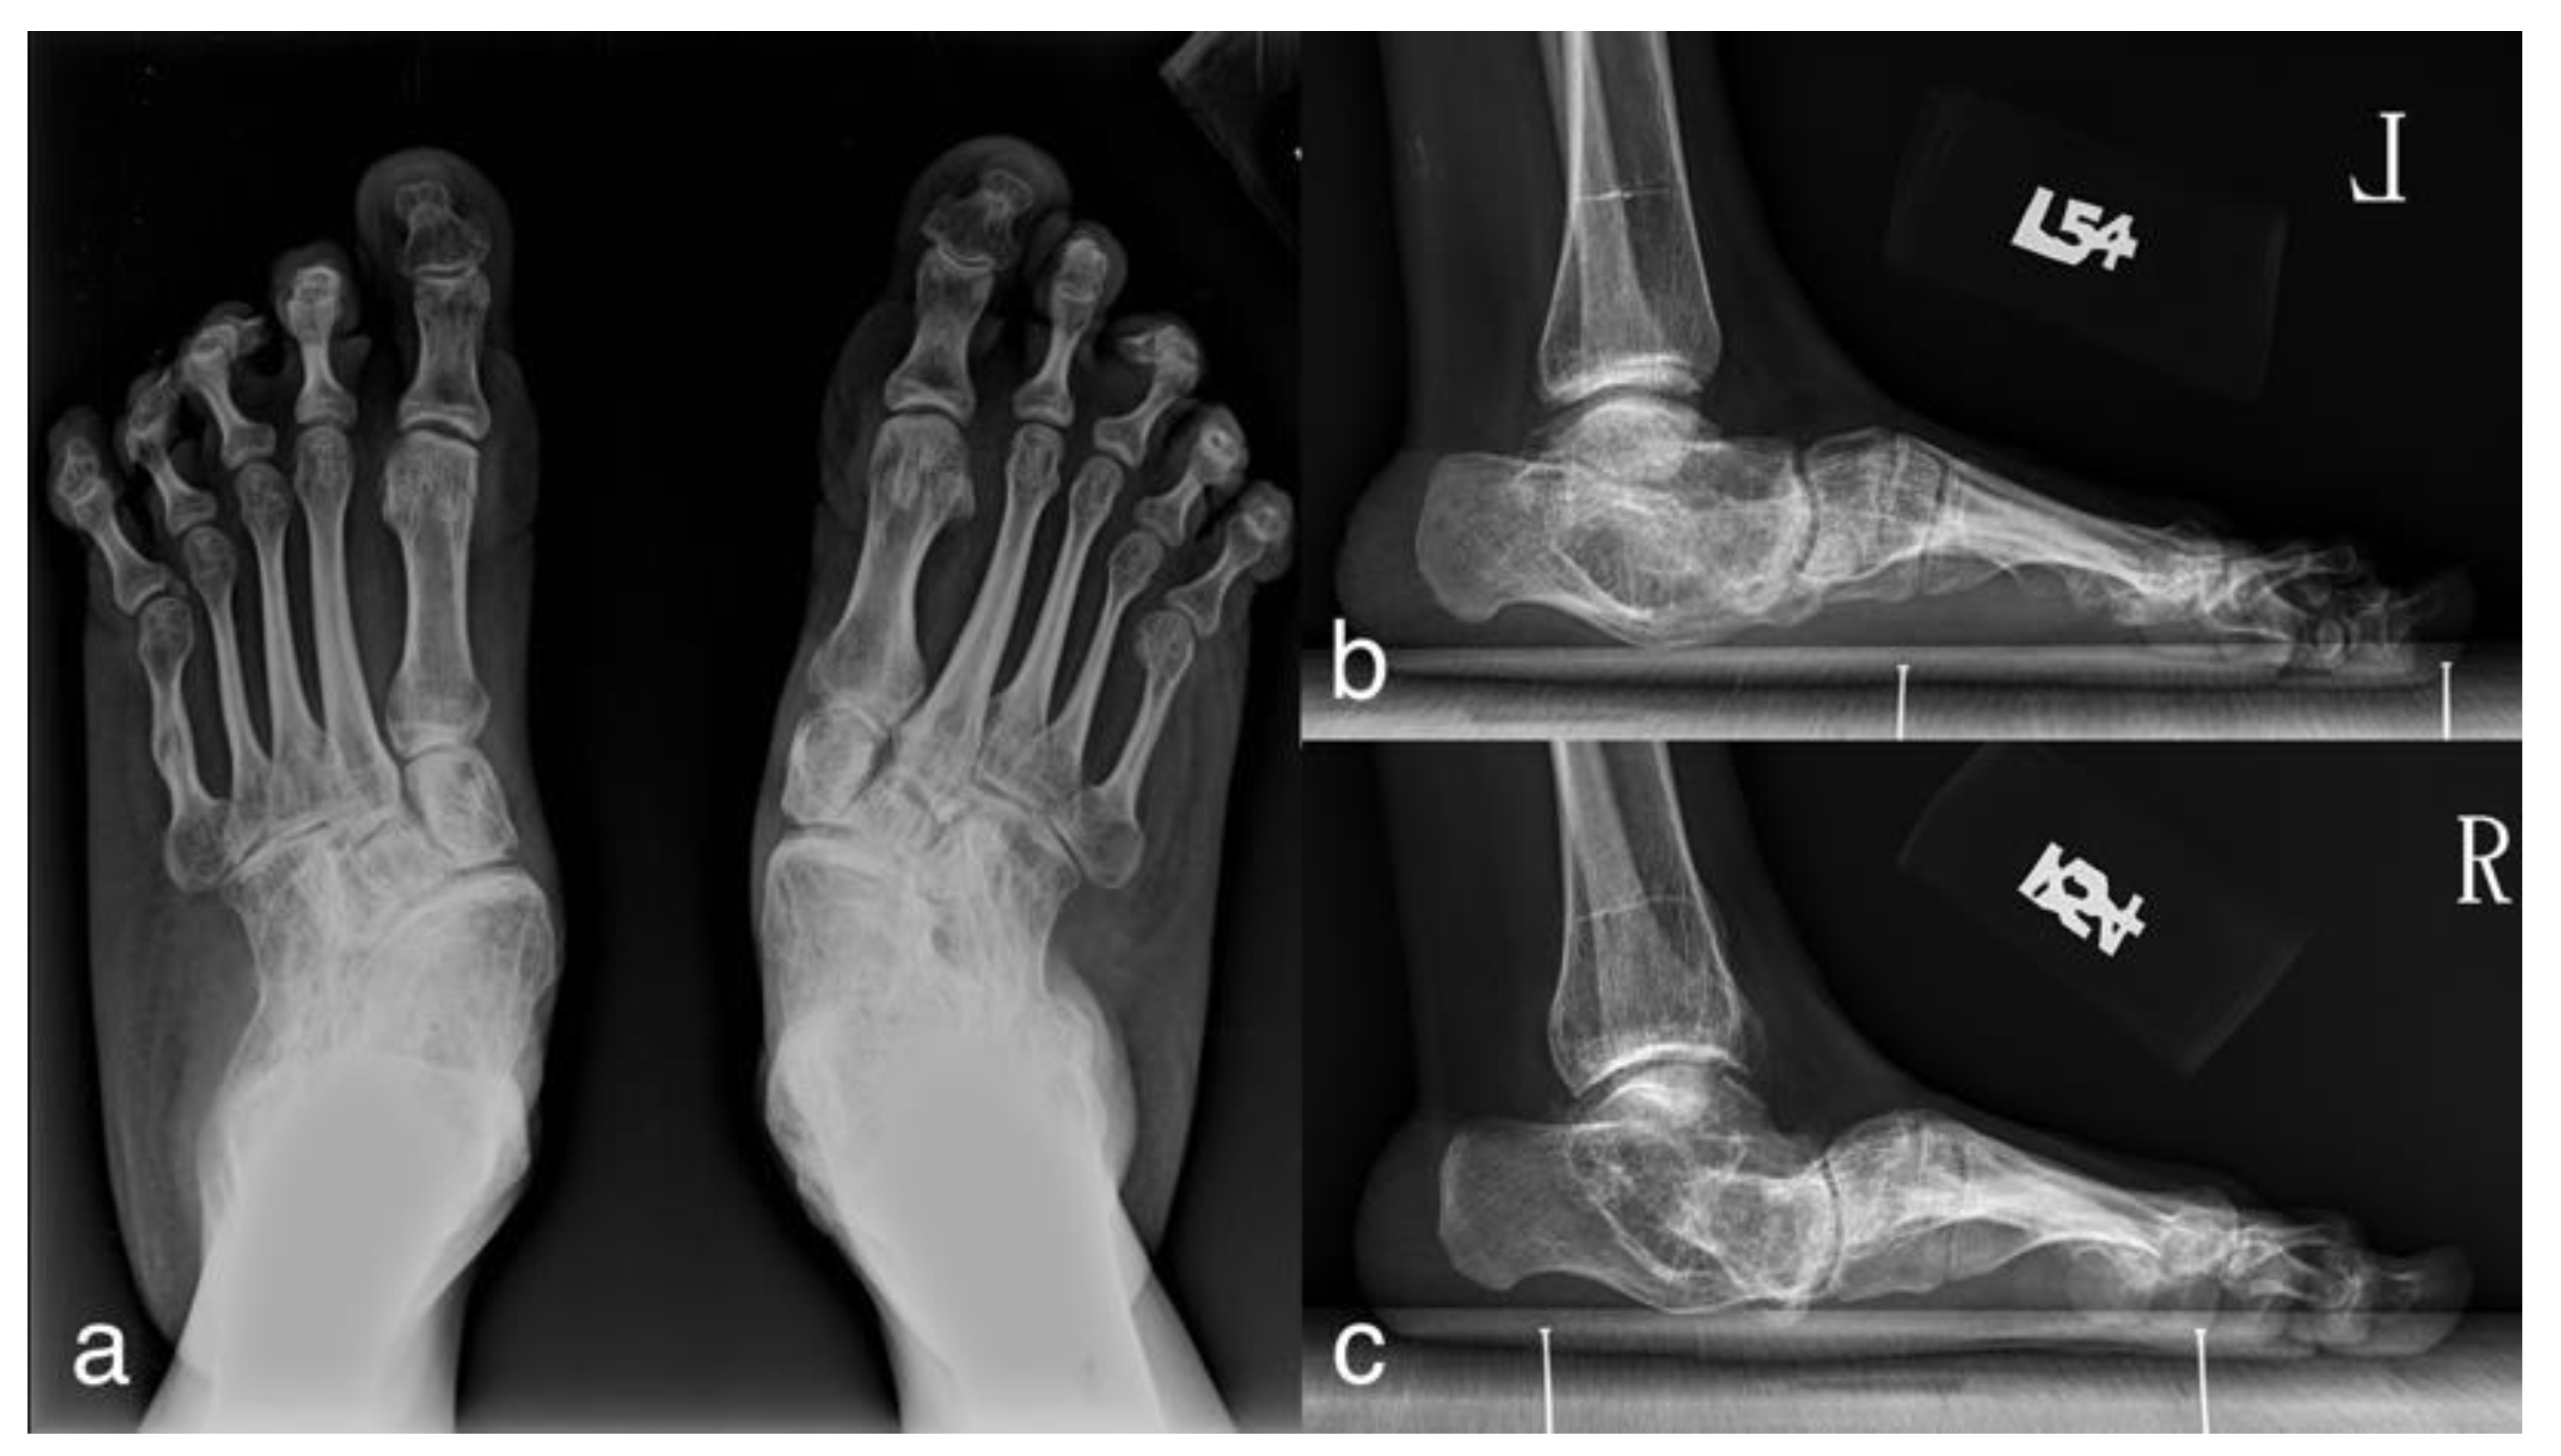

3.2. Case Presentation